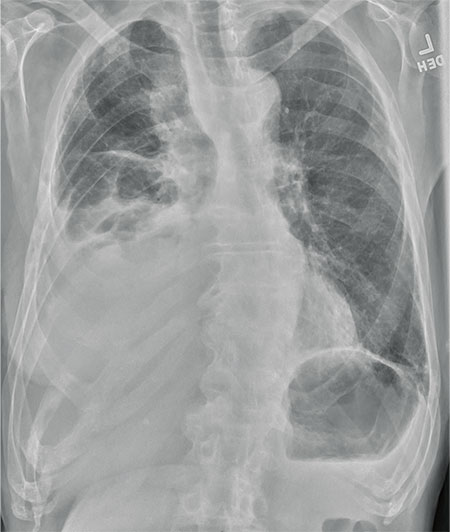

Pneumoperitoneum and subphrenic abscess are two important differential diagnosis of this radiographic sign which can be excluded out when normal plicae circulares or haustral markings of the colon is seen under the right diaphragm. If youre experiencing mild discomfort in your diaphragm take a few minutes to concentrate on deep breathing. Treatment depends on the type of hiatal hernia you have and on your symptoms.

Place one hand on your abdomen and breathe deeply. Reduced number of alveoli air sacs required for normal breathing. In severe cases when there is no simple treatment that can relieve dyspnea your doctor may prescribe morphine. Congenital diaphragmatic hernia CDH. There is usually a long history of heavy smoking. Shortness of breath may be accompanied by wheezing. Diaphragmatic dysfunction caused by transverse myelitis or leukemic infiltration of the cervical spinal cord in a patient with leukemia and shortness of breath. To treat phrenic nerve irritation This condition can be managed with a breathing pacemaker which takes over the responsibility of sending messages to the diaphragm. The cause for shortness of breath was thought primarily due to stable angina on tread mill test positive finding but Chilaiditis syndrome should also be considered as a cause for the shortness of breath.